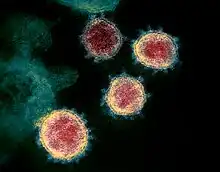

Coronavirus disease 2019 (COVID-19) is an infectious disease caused by severe acute respiratory syndrome coronavirus 2 (SARS-CoV-2). The disease was first identified in December 2019 in Wuhan, the capital of China's Hubei province, and has since spread globally, resulting in the COVID-19 pandemic.

- The SARS-CoV-2 virus is genetically closely related to severe acute respiratory syndrome coronavirus (SARS-CoV), the first pandemic threat of a novel and deadly coronavirus that emerged in late 2002 and caused an outbreak of severe acute respiratory syndrome (SARS). SARS-CoV was highly lethal but faded out after intense public health mitigation measures. By contrast, the novel SARS-CoV-2 that emerged in December, 2019, rapidly caused a global pandemic. The SARS 2003 outbreak ceased in June, 2003, with a global total of 8098 reported cases and 774 deaths, and a case fatality rate of 9•7%, with most cases being acquired nosocomially. In comparison, the Middle East respiratory syndrome coronavirus (MERS-CoV)—another deadly coronavirus, but which is currently not presenting a pandemic threat—emerged in 2012, and has caused 2494 reported cases and 858 deaths in 27 countries and has a very high case fatality rate of 34%. Because MERS-CoV is widespread in dromedary camels, zoonotic cases continue to occur, unlike SARS-CoV, which emerged from wildlife and was eliminated from the intermediate host reservoir.

The new coronavirus SARS-CoV-2 is less deadly but far more transmissible than MERS-CoV or SARS-CoV. The virus emerged in December, 2019, and as of June 29, 2020, 6 months into the first pandemic wave, the global count is rapidly approaching 10 million known cases and has passed 500 000 deaths. Because of its broad clinical spectrum and high transmissibility, eradicating SARS-CoV-2, as was done with SARS-CoV in 2003, does not seem a realistic goal in the short term.- Jason T. Ladner, Sierra N. Henson, Annalee S. Boyle, Anna L. Engelbrektson, Zane W. Fink, Fatima Rahee, Jonathan D’ambrozio, Kurt E. Schaecher, Mars Stone, Wenjuan Dong, Sanjeet Dadwal, Jianhua Yu, Michael A. Caligiuri, Piotr Cieplak, Magnar Bjørås, Mona H. Fenstad, Svein A. Nordbø, Denis E. Kainov, Norihito Muranaka, Mark S. Chee, Sergey A. Shiryaev, John A. Altin; “Epitope-resolved profiling of the SARS-CoV-2 antibody response identifies cross-reactivity with endemic human coronaviruses”. Cell Reports Medicine, 2021; 2 (1): 100189 DOI: 10.1016/j.xcrm.2020.100189

- In 1912, German veterinarians puzzled over the case of a feverish cat with an enormously swollen belly. That is now thought to be the first reported example of the debilitating power of a coronavirus. Veterinarians didn’t know it at the time, but coronaviruses were also giving chickens bronchitis, and pigs an intestinal disease that killed almost every piglet under two weeks old.

The link between these pathogens remained hidden until the 1960s, when researchers in the United Kingdom and the United States isolated two viruses with crown-like structures causing common colds in humans. Scientists soon noticed that the viruses identified in sick animals had the same bristly structure, studded with spiky protein protrusions. Under electron microscopes, these viruses resembled the solar corona, which led researchers in 1968 to coin the term coronaviruses for the entire group.

It was a family of dynamic killers: dog coronaviruses could harm cats, the cat coronavirus could ravage pig intestines. Researchers thought that coronaviruses caused only mild symptoms in humans, until the outbreak of severe acute respiratory syndrome (SARS) in 2003 revealed how easily these versatile viruses could kill people. - Of the viruses that attack humans, coronaviruses are big. At 125 nanometres in diameter, they are also relatively large for the viruses that use RNA to replicate, the group that accounts for most newly emerging diseases. But coronaviruses really stand out for their genomes. With 30,000 genetic bases, coronaviruses have the largest genomes of all RNA viruses. Their genomes are more than three times as big as those of HIV and hepatitis C, and more than twice influenza’s.